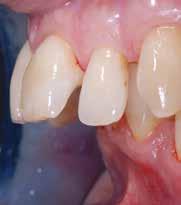

B.M. Bambina di sei anni e mezzo, con malocclusione scheletrica di II Classe, deep-bite over-jet elevato, lieve contrazione dell’arcata superiore, alterazione dell’eruzione dell’elemento dentale 21.

69 68 ESTETICA FUNZIONE POSTURA Valori cefalometrici iniziali ANB ANB 6,20 Posizione del Mascellare SNA 84,20 Posizione della Mandibola SNB 78,00 Angolo Articolare SArGo 132,00 Angolo Goniaco ArGoMe 134,00 Angolo incisivo inferiore Corpo Mandibolare liMand 97,00 Angolo incisivo superiore Base Cranica Anteriore IsCran 107,00 Angolo Interincisivo II 123,00

Controllo dopo cinque mesi di terapia

Fig. 15 > Immagine intraorale frontale.

Fig. 16 > Immagine intraorale laterale destra.

Fig. 17 > Immagine intraorale laterale sinistra.

Fig. 18 > Immagine occlusale superiore.

Fig. 19 > Dettaglio degli incisivi superiori.

Fig. 20 > Sorriso laterale destro.

Fig. 21 > Sorriso laterale sinistro.